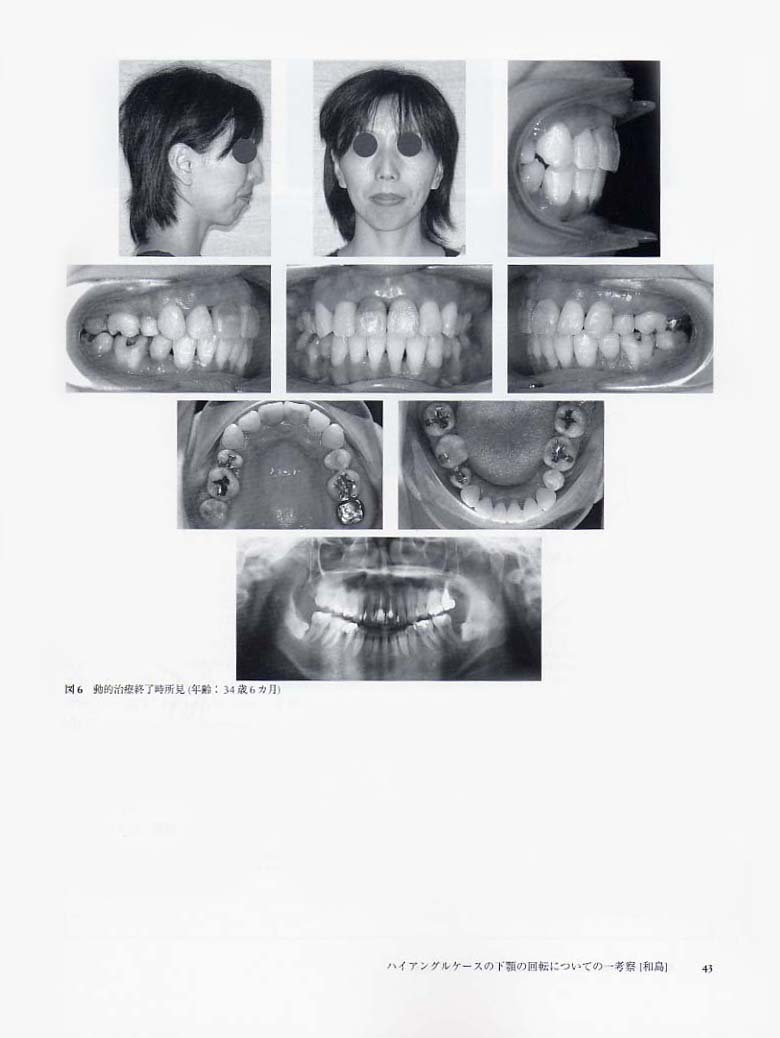

ハイアングルケースの下顎の回転についての一考察(和島)